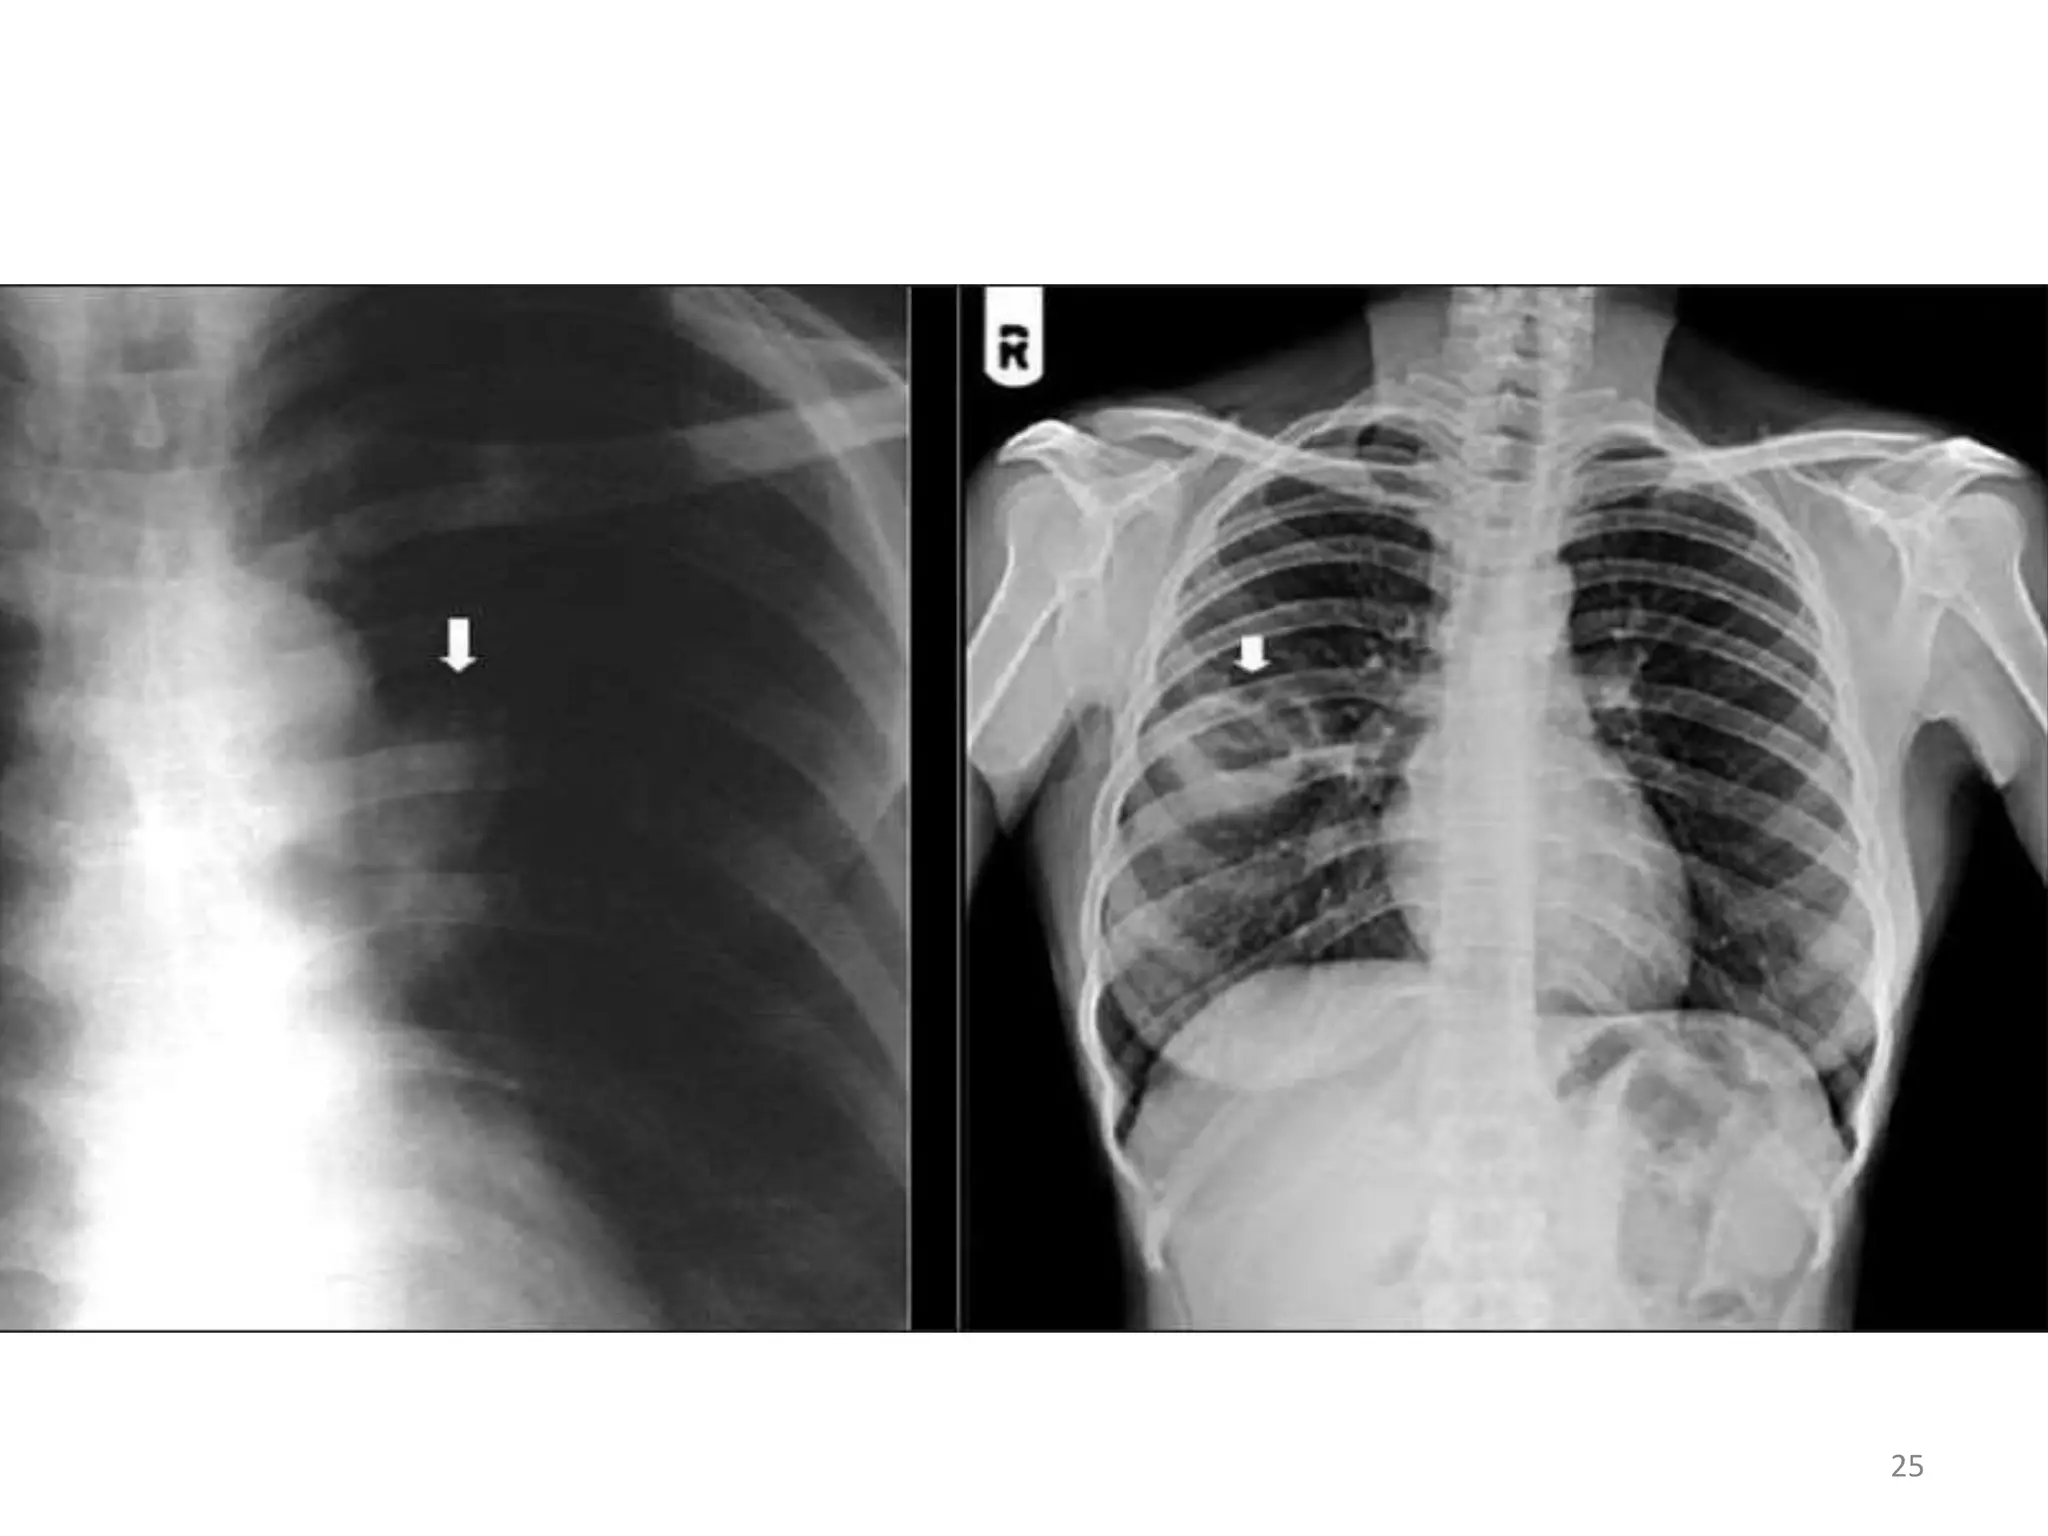

• #19 X ray revealing bilateral, predominantly central, granular opacities and 3 thin-walled air-containing cysts (pneumatoceles) (arrows). This combination of findings is strongly suggestive of Pneumocystis jiroveci pneumonia, which was microscopically confirmed by examination of bronchoalveolar lavage fluid.